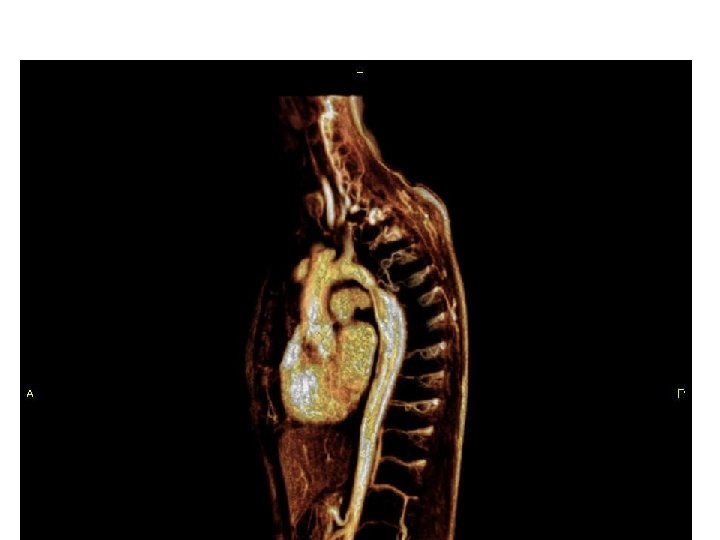

Transpozice velkých cév – Jatene operace